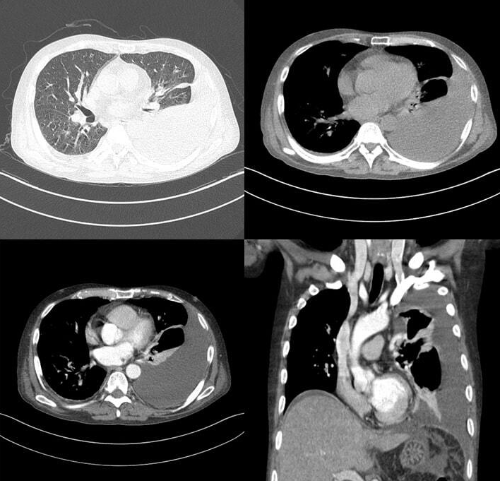

원형의 큰 기계에 들어가 X선을 이용하여 인체의 횡단면상을 영상화하여 진단하는 검사입니다.

특히 선명한 단면 영상을 보여주기 때문에 일반 X선 촬영, 초음파 검사에 비해 직관적이고 해상도가 뛰어나다는 장점이 있습니다.

- 인체 조직을 상세하고 명료하게 나타낼 수 있어 정상 조직과 병변 조직을 구분하여 보여줌

반면에 흉부 CT 검사는 폐와 폐의 실질 조직 내 질환, 기관지 부위의 병변을 진단하기 위해 시행하는 검사입니다.

5mm 이하의 아주 작은 결절도 발견할 수 있으므로 현재로서는 가장 유효하고 정확한 검진 방법이라 하겠습니다.